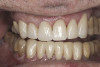

(35.) Postoperative right lateral, closed view.

Figure 35

(36.) Postoperative anterior, closed view. Note the position of the upper and lower canines to provide canine guidance.

Figure 36

(37.) Postoperative left lateral, closed view.

Figure 37

Based on examination of the mounted models, it was decided to treat the patient in centric relation and an additive equilibration approach was used to idealize the planes of occlusion. On the articulator, the patient’s first point of contact in centric relation was the starting point and an additive equilibration technique was implemented, building the teeth to meet ideally at the patient’s first point of contact. A diagnostic wax-up was completed on the mounted models to determine where the anterior and posterior teeth needed to be in space. A template from the wax-up was used to fabricate the anterior provisional restorations. The anterior teeth were restored with full-coverage restorations, creating ideal stops between the lower incisal edges and upper cingulums. The maxillary incisal edges were placed to provide proper phonetics and an acceptable esthetic outcome, while still working within the envelope of function. All of these parameters are worked out in the provisionals prior to moving forward with definitive restorations. With the anterior provisionals in place, posterior composite tops were bonded to his existing dentition, creating ideal centric stops on the posterior teeth. The anterior and canine guidance was developed, resulting in immediate separation of the posterior teeth during all excursive movements (Figure 17 through Figure 28). Once the author and patient were happy with the function, esthetics, phonetics, and comfort of the provisionals, an impression of the approved provisionals was taken and sent to the laboratory to use as a guide in the fabrication of the final anterior crowns. With the final restorations delivered, the patient was extremely happy with his new smile. Most importantly, proper anterior and canine guidance in harmony with his envelope of function was achieved, which resulted in comfortable function and immediate separation of the posterior teeth during protrusive and lateral excursions (Figure 29 through Figure 42).